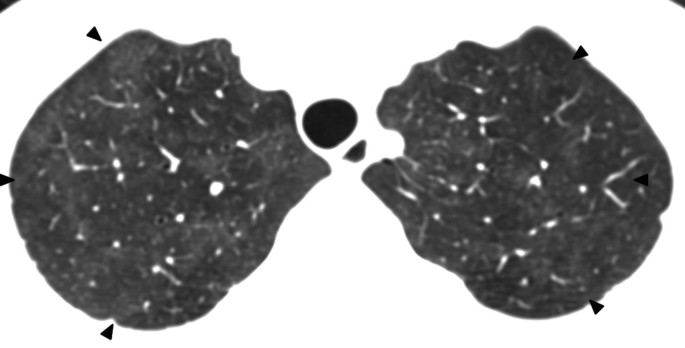

A 36-year-old lady with diffuse large B-cell lymphoma presented with neutropenic fever and cough on the 17th day of the 6th cycle of CHOP chemotherapy (cyclophosphamide, hydroxydaunorubincin, oncovin and prednisolone). Physical examination was unremarkable apart from the low grade fever (38.1°C). On admission she had a low absolute neutrophil count (ANC) (0.6x10*9/L), high erythrocyte sedimentation rate (ESR) (50 mm/h) and high C-reactive protein (CRP) level (12.3 mg/l). Chest radiograph was normal (Figure1). Initial septic workup was negative, which included sputum bacterial culture, sputum acid fast bacilli (AFB) smear and culture, bacterial and fungal blood culture, early morning urine AFB smear and culture. Thoracic CT was performed subsequently, which showed bilateral patchy ground glass opacities without zonal predominance (Figure2). Repeated sputum culture yielded heavy growth of S. maltophilia, which was sensitive to Ceftazidime, Cotrimoxazole, Levofloxacin, Ticarcillin/ Clavulanate, and resistant to Imipenem. After cessation of chemotherapy and commencement of Piperacillin/ Tazobactam (Tazocin) and Gentamycin, which later switched to Ciprofloxacin, her fever subsided and ANC normalized. Her chest radiographs were all along normal despite abnormal thoracic CT. Three months later her thoracic CT showed complete resolution of the ground glass opacities (Figure3).

To the best of our knowledge, there is only one case report describing the CT features of S. maltophilia[23]. In that case, multifocal areas of air-space consolidation, ground-glass attenuation areas, small centrilobular nodules and bronchial wall thickening were present. In our series, the sole CT finding of patient 1 is bilateral patchy ground glass opacities without zonal predominance. Air-space consolidation, ground glass opacities, numerous centrilobular nodules and bronchial wall thickening are noted in patient 2. These are similar to those described in prior case report. Compared with that reported case, the only new imaging finding in patient 2 is bilateral cylindrical bronchiectasis. Among all three cases, diffuse ground glass opacities without zonal predominance is the most consistent CT features of S. maltophilia pneumonia. Other imaging findings such as bilateral multifocal areas of air-space consolidation and centrilobular nodules can be occasionally found. Bronchiectasis likely represents the later stage of pneumonia. However, since these imaging features and pattern are not specific nor diagnostic, the final diagnosis of S. maltophilia pneumonia still relies on microbiology results.

Stenotrophomonas maltophilia is a rare yet important globally emerging opportunistic pathogen. The most consistent CT features of S. maltophilia pneumonia is diffuse ground glass opacities without zonal predominance. Bilateral multifocal areas of air-space consolidation, centrilobular nodules, bronchiectasis and bronchial wall thickening are occasionally found. Due to its supreme sensitivity, the role of thoracic CT in the detection and exclusion of pulmonary infection, including S. maltophilia pneumonia, in neutropenic febrile patients cannot be overstressed.